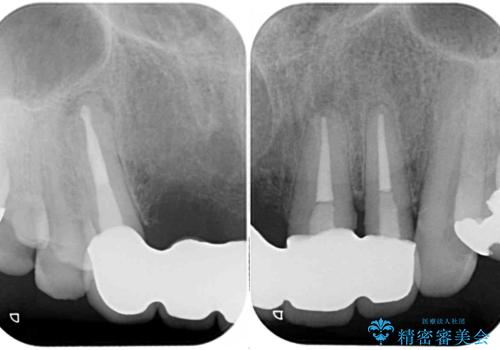

土台となる歯は根管治療の結果が良好ではないため、根管治療からやり直しをした後、オールセラミックブリッジにて補綴することとしました。

露出していた歯根や金属の縁が見えてしまい、人前で話すときの目線が気になっていらっしゃいましたが、歯肉の位置に縁を合わせてことで自然な仕上がりとなりました。

露出していた歯根が覆われるため、歯冠が長く見えてしまうことが懸念されましたが特に気になることはなく、患者様には大変満足していただきました。